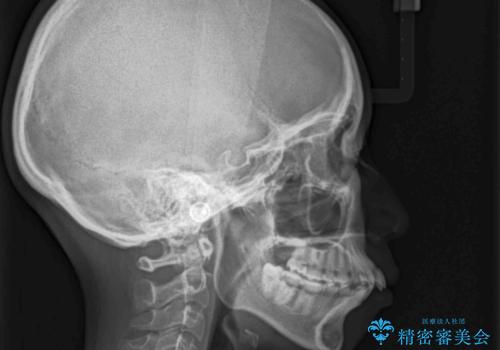

目立たない裏側装置 ハーフリンガルの抜歯矯正

- 口元の突出感を気にして来院された患者様です。

上下左右の第一小臼歯4本を抜歯して口元を下げる治療計画としました。

目立たない装置が希望であったため、上顎が裏側装置である、ハーフリンガル装置を選択されました。